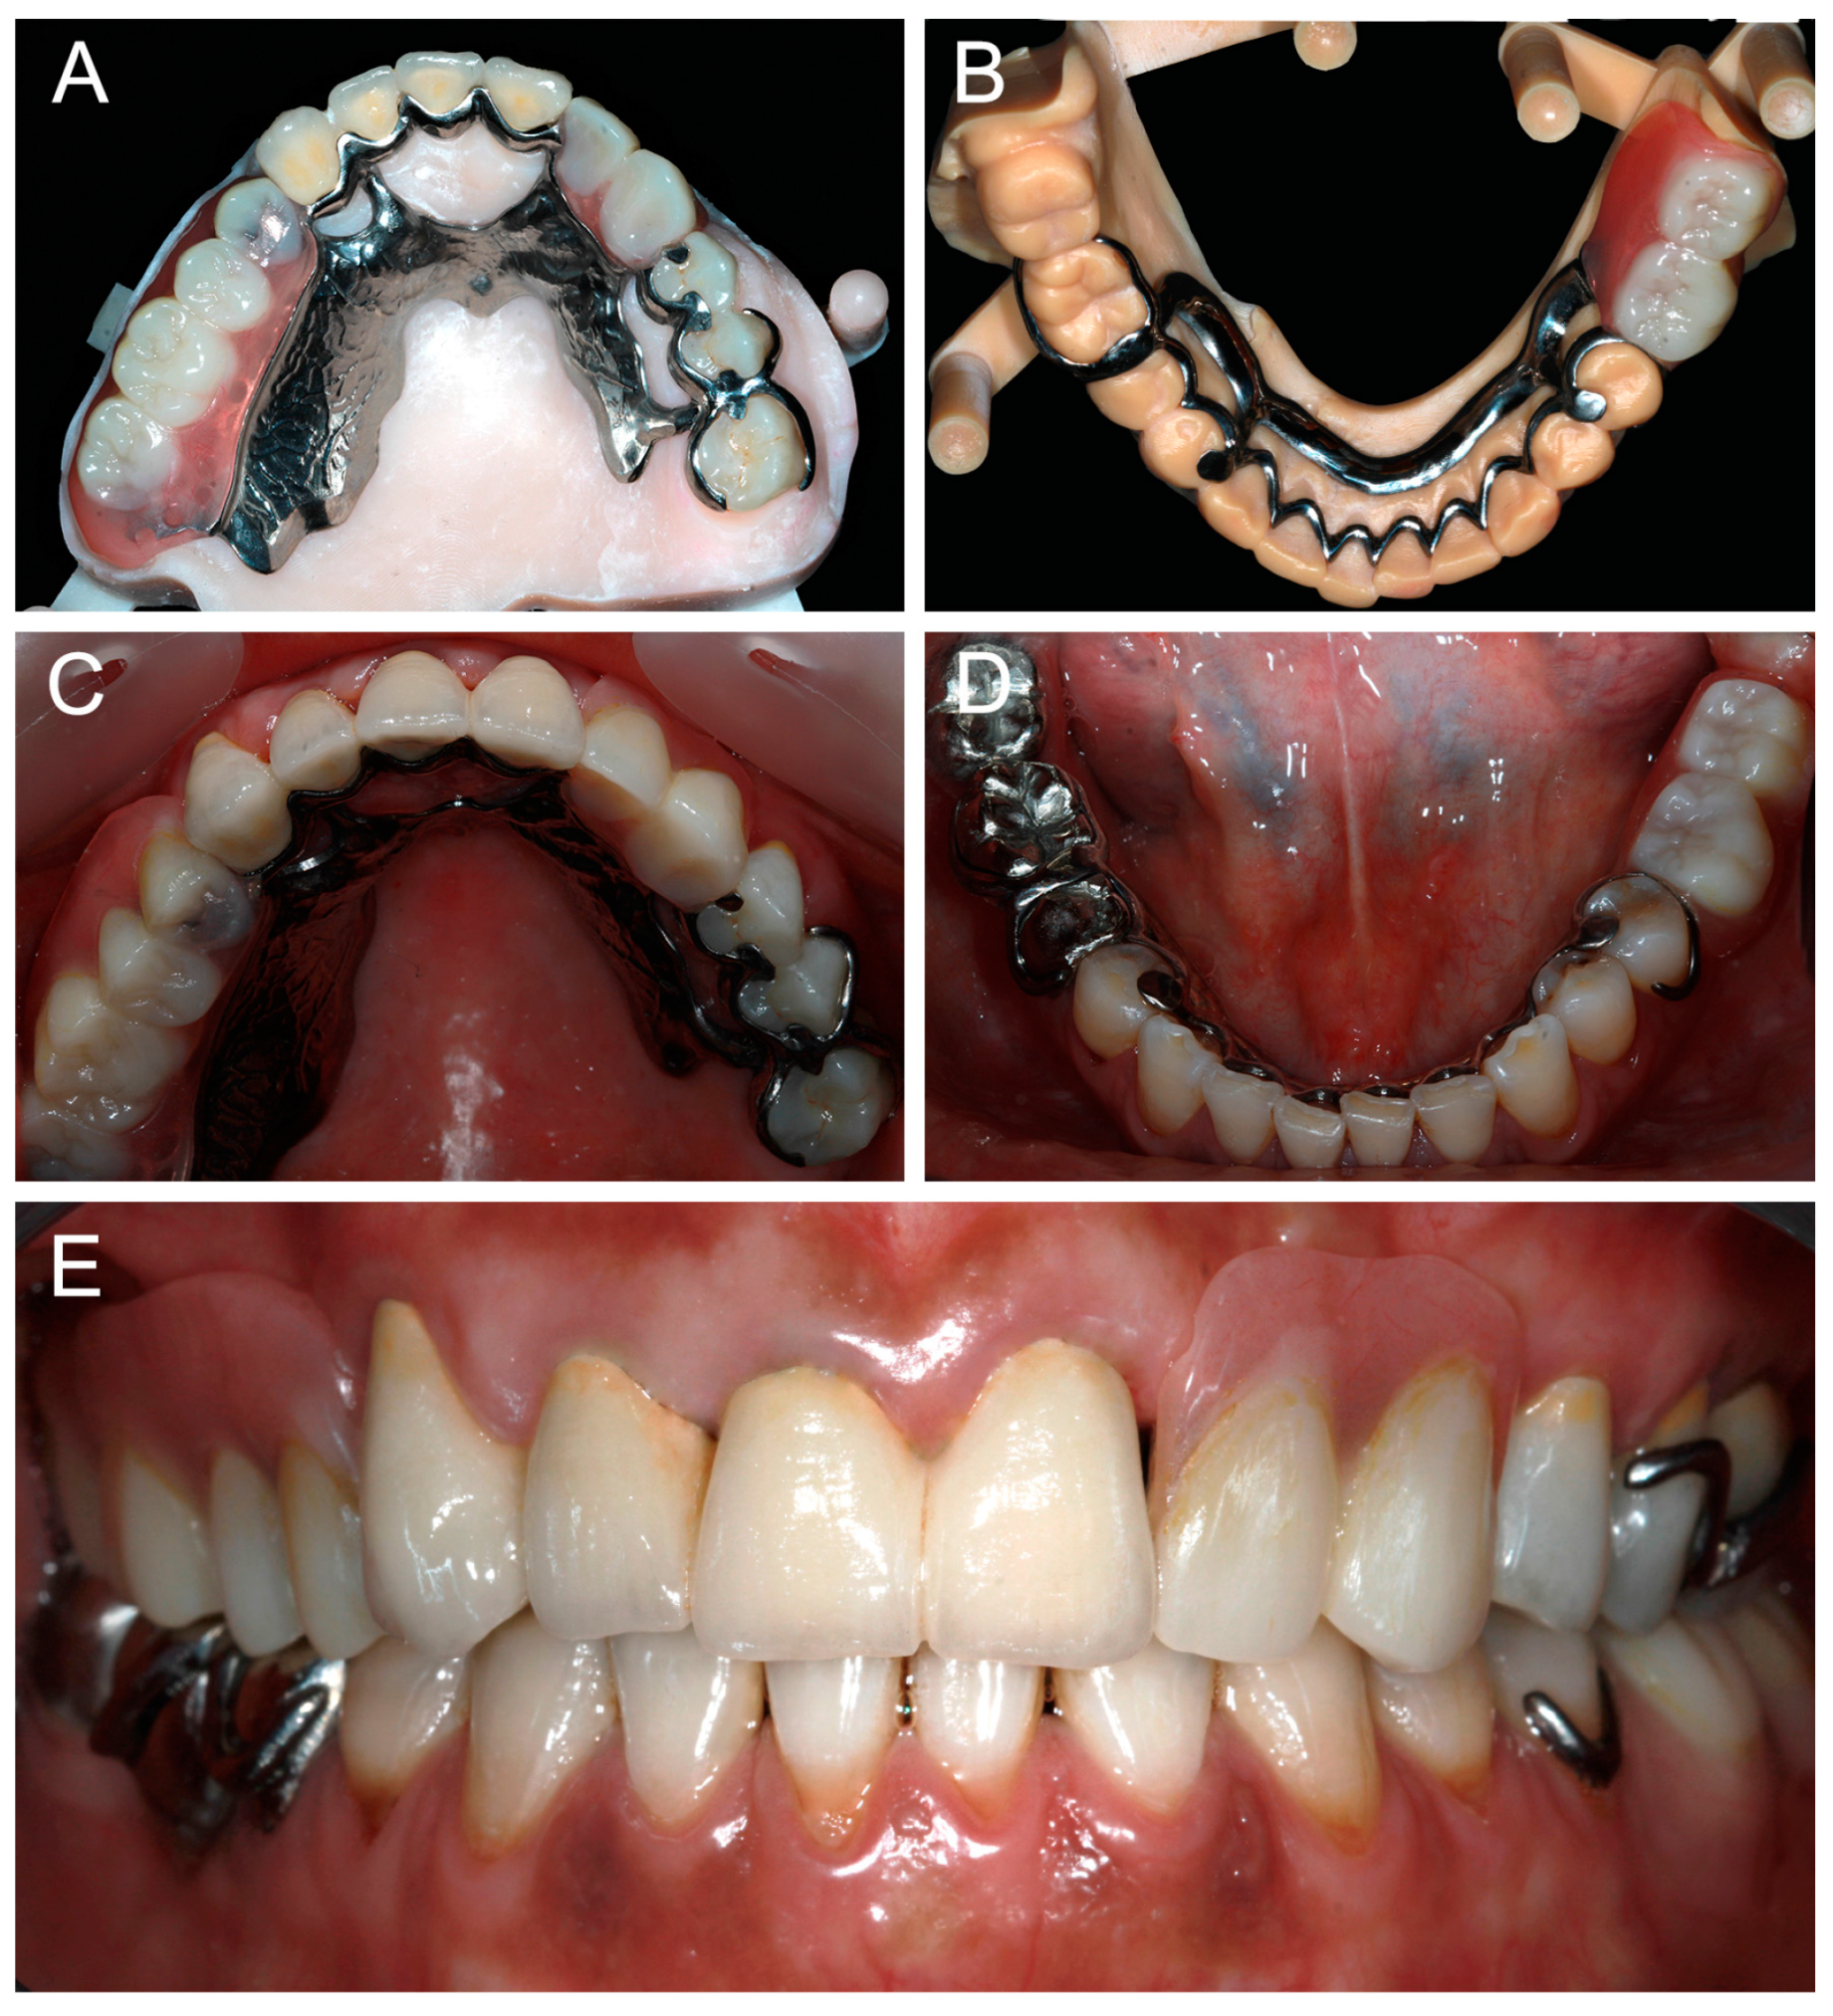

FDPs and RPDs were tried-in intraorally. Stability, retention, esthetic, phonetics, and occlusion were evaluated. Minor adjustments were made where needed. FDPs were definitively cemented and the RPDs were inserted (Figure 7). Occlusion was again verified. Maintenance instructions and oral hygiene methods were provided to the patient.

Figure 7.

Occlusal views of maxillary and mandibular definitive prostheses: (A,B) on the printed casts; (C,D) in clinical situation; and (E) frontal view of prostheses in clinical situation.